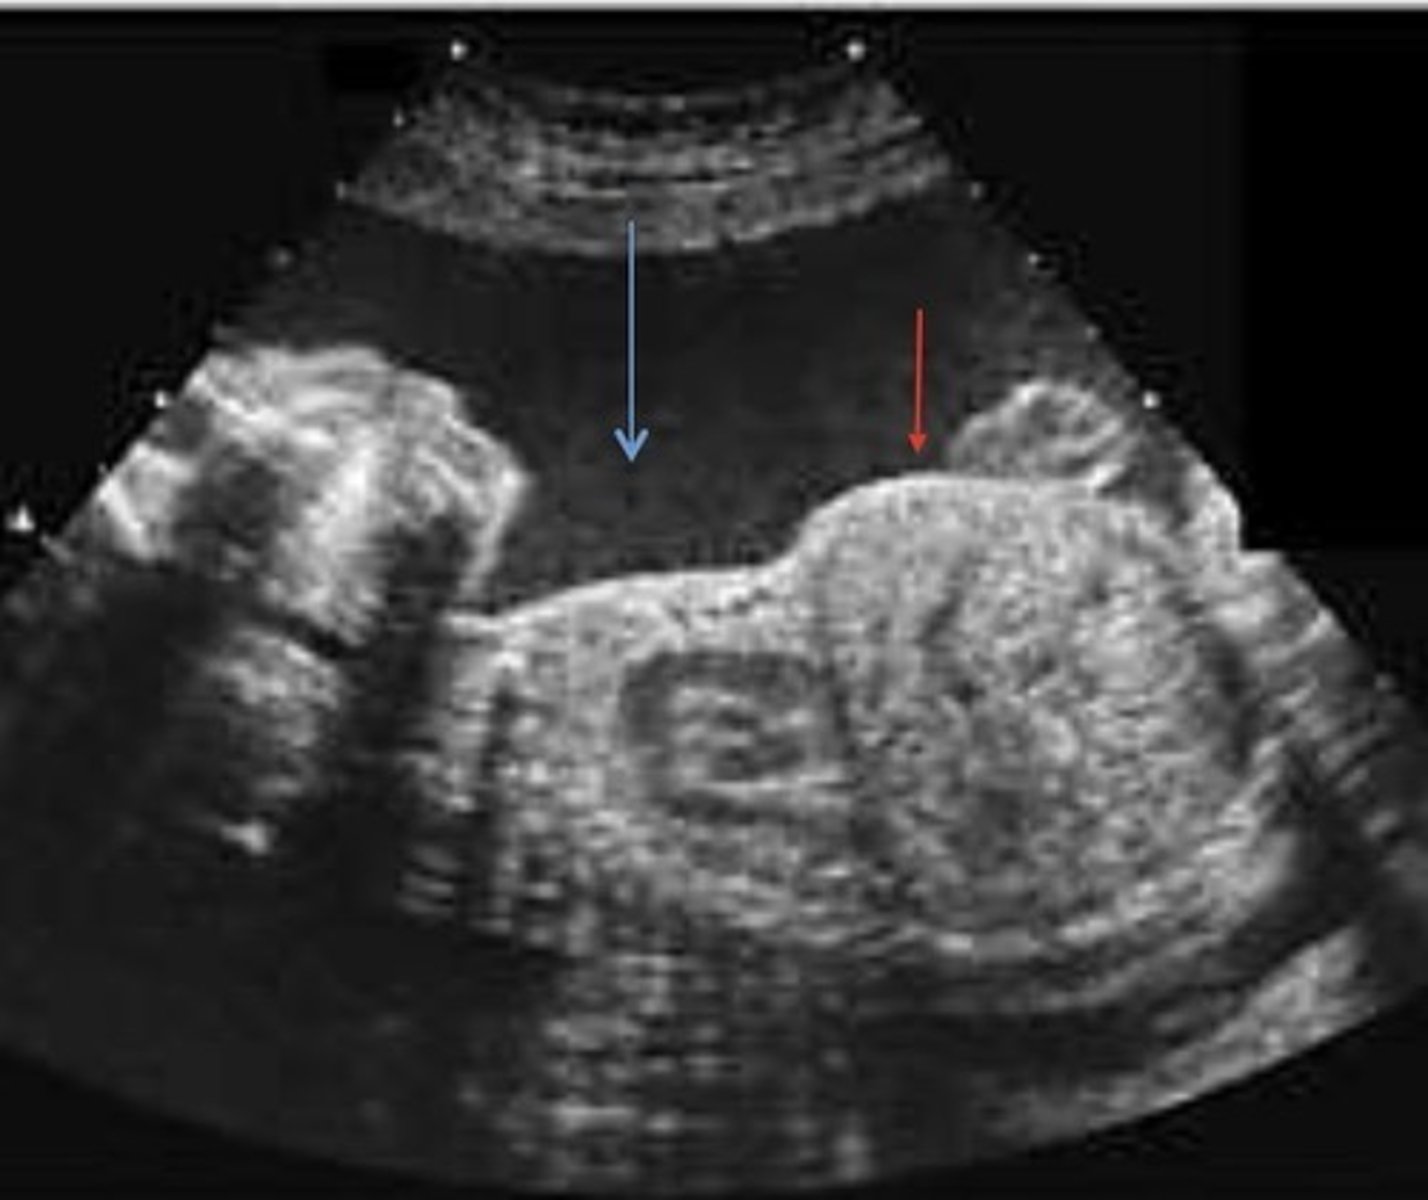

Posterior Urethral Valve Obstruction

Only in boys

Causes bilateral hydronephrosis

Thick bladder walls

Keyhole bladder appearance